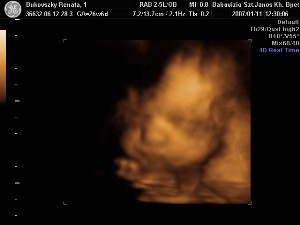

25.héten